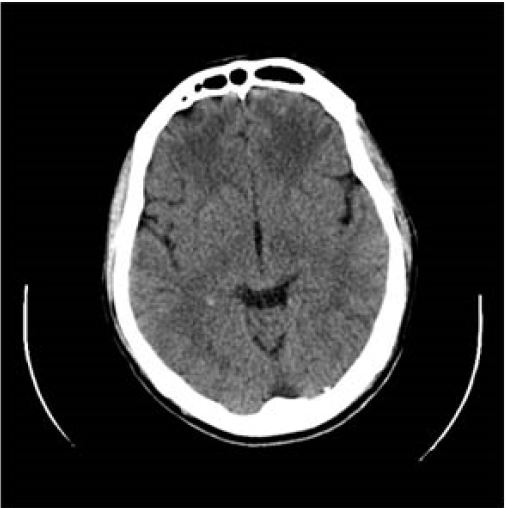

Se observa que, en la malaria cerebral, los parásitos obstruyen vasos sanguíneos importantes en la estructura cerebral logrando inflamar al cerebro. En casos más graves, se han observado efectos más severos de la malaria, afectando la estructura cerebral e incluso induciendo el coma. Todo ello, como consecuencia del daño producido en el sistema autónomo, cracaterizado por su papel de mediador en las respuestas fisiológicas automáticas.

Hasta la actualidad, no se conocen con exactitud los mecanismos fisiopatológicos de la enfermedad. Sin embargo, es sabido que existen factores como la obstrucción vascular que influyen mayormente en el desarrollo de isquemias cerebrales.

En lo que respecta a los eventos vasculares de la malaria, estos suelen afectar mayormente a la sustancia blanca del cerebro. Cuando ocurre, es común observar en los pacientes una disminución de la velocidad de procesamiento, un riesgo elevado de desarrollar alzhéimer, demencia y afasia. Así como síntomas de dislexia, apraxia y disfasia.